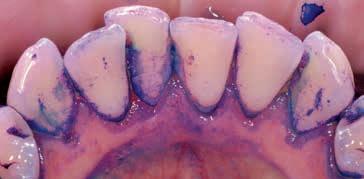

16 02 ANFÄRBEN Das Plaque-Färbemittel sollte auf allen Zahn –und Implantatoberflächen sowie auf Restaurationen und kieferorthopädischen Apparaturen angewendet werden. Das Sichtbarmachen des Biofilms ist ein sehr wichtiger Schritt im GBT Protokoll. WARUM BIOFILM ANFÄRBEN? Mit der GBT soll der Biofilm zu 100% entfernt werden. Sichtbarer Biofilm kann schneller und effektiver entfernt werden. Was man sieht, wird auch entfernt. Darüber hinaus wird der Patient durch die GBT motiviert, Ihre Anweisungen für die häusliche Mundhygiene (OHI) umzusetzen. Entfernung der Farbe = Entfernung des Biofilms. 1º VOR DEM ANFÄRBEN 2º AUFTRAGEN DES 2FÄRBEMITTELS º ABSPRÜHEN 3º NACH DEM ANFÄRBEN

VORHER ANGEFÄRBT

VOR DEM ANFÄRBEN NACH DEM ANFÄRBEN Abbildungen: Mit freundlicher Genehmigung von Prof. Magda Mensi

Die gemeinnützige deutsche Verbraucherorganisation „Stiftung Warentest” (Test 7, 2015) hat bekannt gegeben, dass bei einer herkömmlichen Zahnreinigung nur 50% des Biofilms in den Interdentalbereichen entfernt wird. Biofilm ist mit bloßem Auge nicht immer zu erkennen. Durch das Anfärben wird dieser sichtbar gemacht und somit vollständiger entfernt (Siehe Pilotstudie: Verbessert das Anfärben der Plaque die Ergebnisse einer PZR? Von Dr. Klaus-Dieter Bastendorf, Dr. Nadine Strafela-Bastendorf und Petra Mann)

KIEFERORTHOPÄDIE Biofilm ist jetzt sowohl an den Zähnen als auch an den Brackets sichtbar. Das ist ein wichtiger Vorteil bei der Patientenmotivation und der kompletten Entfernung von Biofilm mit AIRFLOW®.

MACHEN SIE DEN BIOFILM SICHTBAR DIE FARBE ERLEICHTERT DIE ENTFERNUNG DES BIOFILMS OHNE BIOFILM IST ZAHNSTEIN BESSER ZU ERKENNEN.